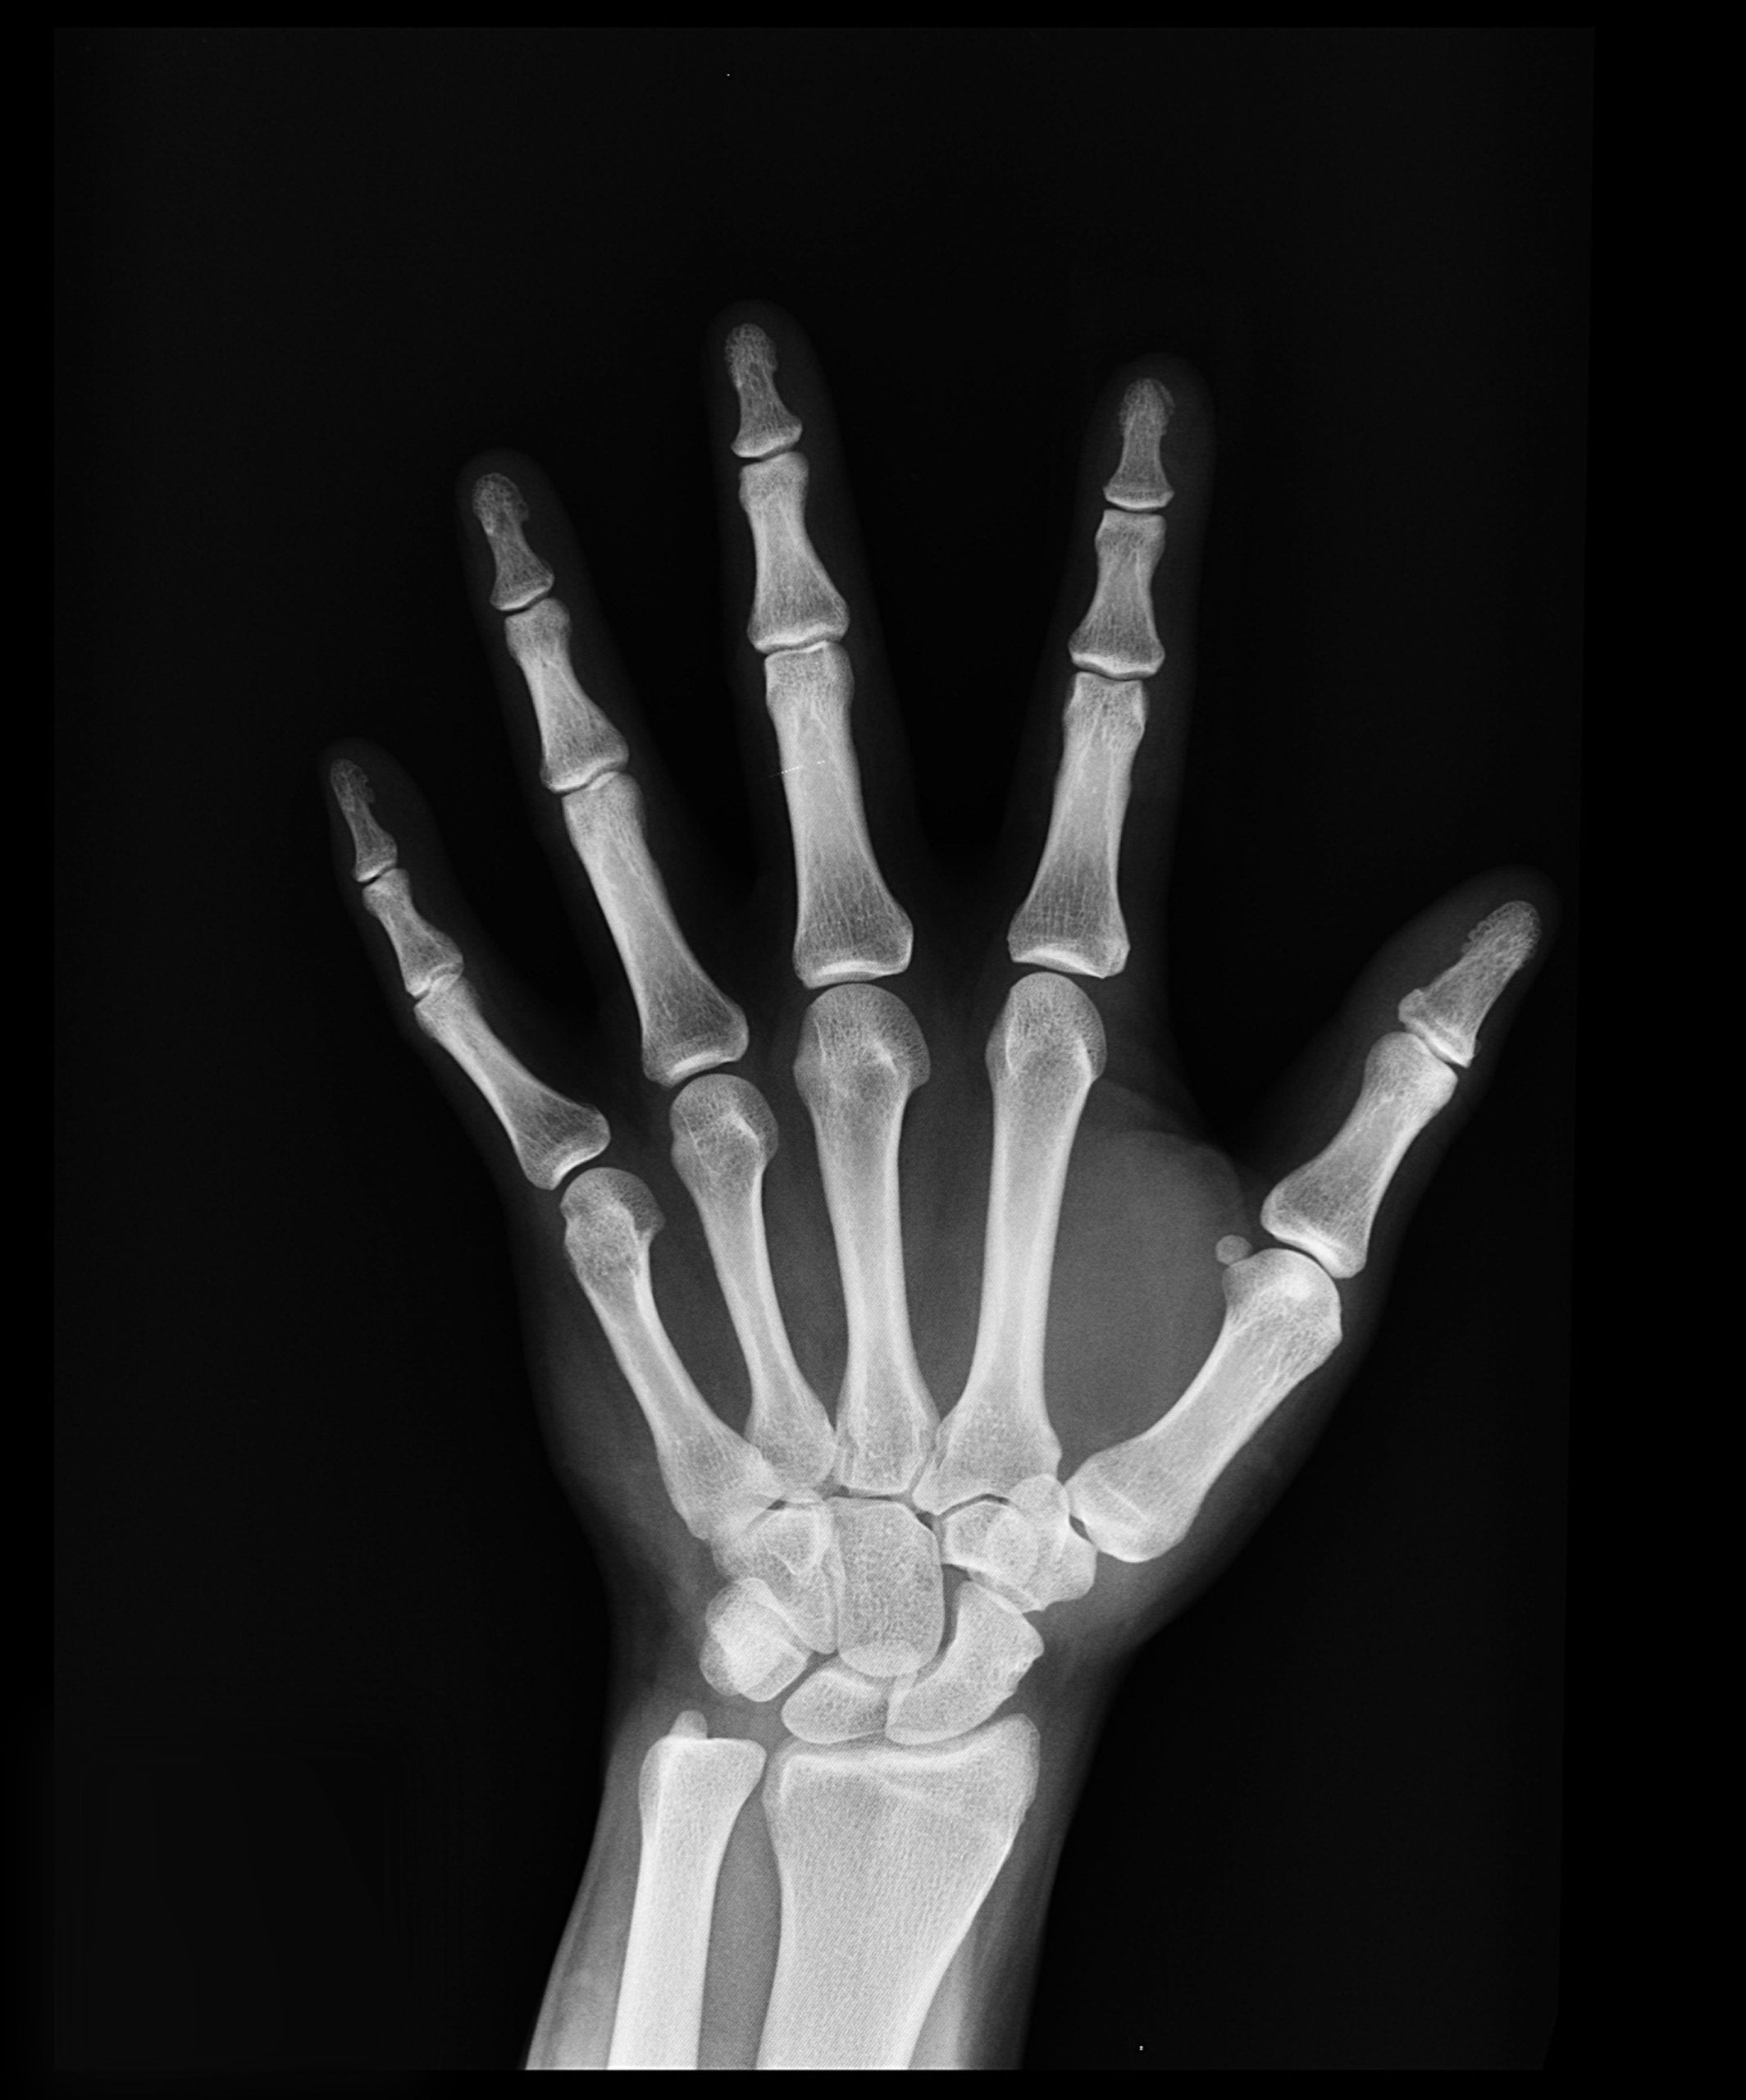

Alrededor de 24.000 españoles podrían padecer hipofosfatasia sin saberlo, según los datos de un estudio, publicado en la revista científica ‘Scientific Reports’ del grupo Nature’, realizado por investigadores del CIBER de Fragilidad y Envejecimiento Saludable (CIBERFES) en el Instituto de Investigación Biosanitaria de Granada.

El grupo de investigadores ha observado que el 62 por ciento de los pacientes con niveles de fosfatasa alcalina por debajo del rango de normalidad son portadores de una mutación en el gen codificante de FANET. Sin embargo, aún no se han puesto en marcha programas de detección precoz, por lo que la investigadora Beatriz García ha tildado la enfermedad como «infradiagnosticada».

«Este estudio evidencia que es fundamental establecer una evaluación clínica correcta para realizar un diagnóstico adecuado de este trastorno y proporcionar un tratamiento correcto a los pacientes afectados», ha añadido.